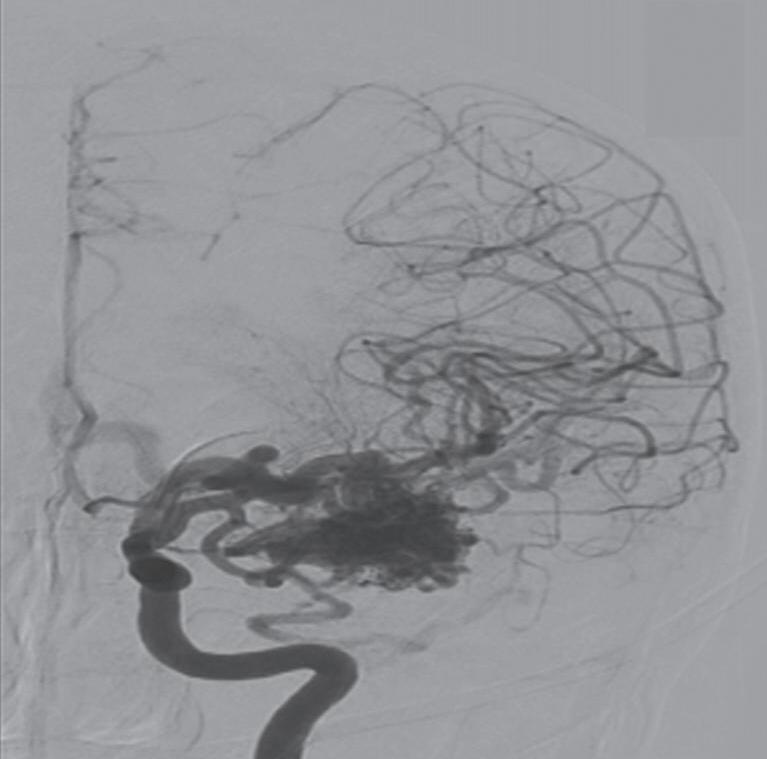

Fig. 1-8. (a-c) RNM T1 com contraste, cortes sagital (a), coronal (b) e axial (c) demonstrando MAV não rota com nidus localizado no lobo occipital à esquerda (setas longas). (d) Arteriografia digital cerebral com injeção de contraste via carótida direita (AP) mostrando a contribuição da carótida direita na irrigação da MAV contralateral. (e,f) Com injeção de contraste via carótida esquerda, em Perfil e AP respectivamente, observa-se nidus compacto nutrido por ramos da artéria cerebral média à esquerda e a veia de drenagem precoce se dirigindo para o seio sagital superior. Projeções em AP (g) e em perfil (h) demonstrando a contribuição do sistema vertebrobasilar por meio de ramos distais da artéria cerebral posterior à esquerda e drenagem para os seios sagital superior e sigmoide à esquerda (setas curtas).